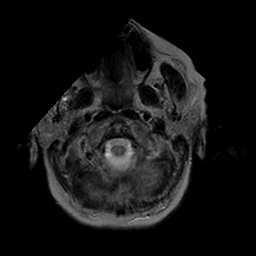

Stroke:T2-weighted MR #2 -- Slice #0

[Home][Help][Clinical] Slice 0